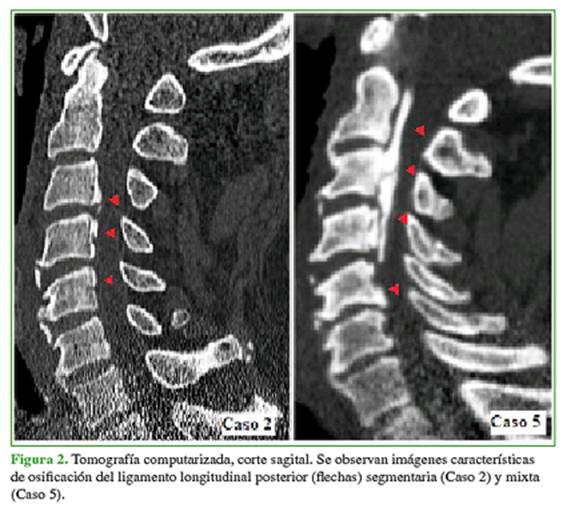

Según la clasificación morfológica de la OLLP, un caso (20%) era tipo A o continua (caso 1); uno (20%), tipo B o segmentaria (caso 2); uno (20%), tipo C o combinada (caso 5); dos (40%), tipo D o limitada al espacio discal (casos 3 y 4) (Figuras 2 y 3).

Se describieron las siguientes variables de estudio: edad, sexo, comorbilidades, antecedente traumático, tiempo preoperatorio (>72 h o <72 h), estado neurológico inicial según la escala de la American Spinal Injury Association (ASIA),23 tipo de OLLP según la clasificación morfológica: (A) continua, (B) segmentaria, (C) combinada y (D) limitada al espacio discal (Figura 1),24 extensión de la mielopatía según los niveles cervicales (imagen hiperintensa en la secuencia T2 de RM), tratamiento realizado (quirúrgico o conservador), tipo de cirugía (técnica y vía de abordaje), evolución neurológica posterapéutica (estable, mejoría o deterioro neurológico) y complicaciones (relacionadas con el trauma y la intervención).